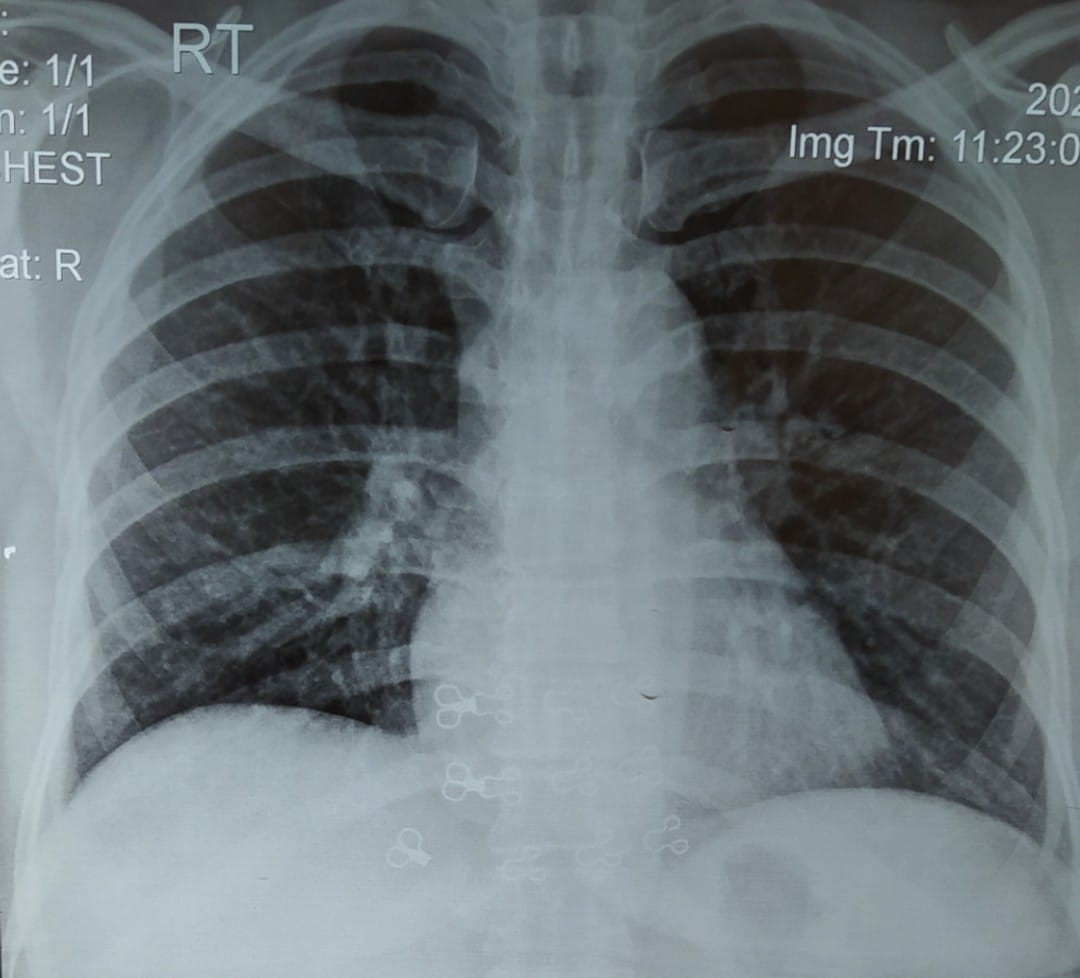

A 45 year old man presents to your clinic with complaints of increasing shortness of breath over last 6 months.

He also gets occasional episodes of dry cough when walking or going up stairs.

He is afebrile / normal Temperature and oxygen saturation is 89 Percent on air .

You organise a chest X ray which is given below:

1. What are findings on chest X ray?

2. What is the most likely Diagnosis?

Interstitial Lung Disease (ILD) Interstitial Lung Disease (ILD) refers to a group of problems in the lung that affects the “interstitium”.

The interstitium refers to the tissue area in and around the wall of the airsacs (alveoli) of the lung area where oxygen moves from the alveoli into the the capillary network (small blood vessels) that covers the lung like a thin sheet of blood.

Once the oxygen crosses the intersitial space it enters the bloodstream and is delivered to the vital organs of your body. ILDs cause this interstitial space to become inflammed or scarred making it more difficult for oxygen.